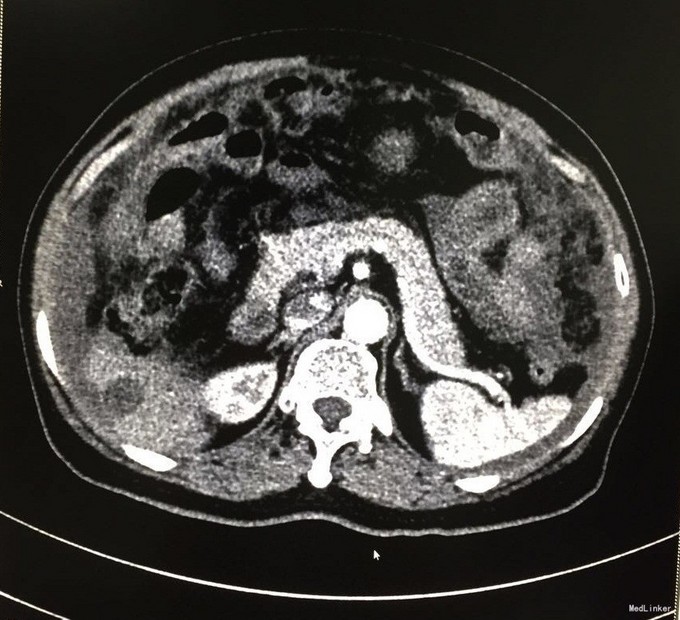

查体:腹膨隆,可及一包块,质中,活动可,边缘不清,位置较固定,无红肿热痛,无压痛。 辅查:我院CT:盆腔巨大囊性肿块,大小约15x10cm,考虑附件来源恶性肿瘤,囊腺癌可能;肝内一结节状稍低密度影,增强后轻度强化,转移瘤可能;胆囊多发结石;盆腹腔积液。肿瘤标志物:CEA:33.2U/mL。

入院诊断:腹腔肿物、胆囊结石、腹水。入院后行剖腹探查术,术中见腹腔大量胶冻样物约5000ml,左卵巢见一20x20cm囊性包块,包膜不完整,可见破溃口,内含胶冻样物,右附件及子宫未见明显异常。阑尾见3x3cm大小的粘液样肿块,腹膜、大网膜、肠管表面均有胶冻样物覆盖。遂行腹式双附件切除术+回盲部肿物切除术+腹膜活检术。术中冰冻病理示:左卵巢粘液囊腺瘤,局部增生活跃。术后病理示:左卵巢粘液性囊腺瘤,阑尾低级别粘液性腺瘤。术后诊断:左卵巢粘液性囊腺瘤并自发破裂,阑尾低级别粘液性腺瘤,胆囊结石。